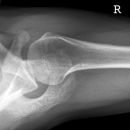

Schulter axial

Schulter axial liegend (caudo-cranial):

Patient in Rückenlage, möglichst weit an Tischkante, Körperachse parallel zum Tisch, Arm in Schultergelenk rechtwinklig abduzieren und unterpolstern, so dass das Schultergelenk in Kassettenmitte kommt, Kassette senkrecht zum Tisch, hinter die Schulter möglichst weit an den Hals geschoben, Kopf zur gesunden Seite drehen.

Schulter axial sitzend:

1. Möglichkeit: Patient sitzt auf dem Stuhl, Arm möglichst weit abduziert, Kassette unter die Axilla bzw. den Oberarm weit auf die auf dem Buckytisch gelagerte Kassette gezogen, Kopf immer zur Gegenseite drehen.

2. Möglichkeit: Patient sitzt auf dem Stuhl, Arm möglichst weit abgespreizt, Kassette auf der Schulter, evtl. mit 15° Keil unterpolstern, Kassette dem Patienten bis an den Hals schieben.

Röhre 90° caudo-cranial, zielt auf Humeruskopf (Axilla) fast parallel zur Körperachse auf das letzte Drittel der Kassette.

bei 1. senkrecht oder 15-20° ellenbogenwärts auf die Schultermitte und Kassette.

Bei 2. von unten in die Axilla senkrecht auf das letzte Drittel der Kassette.

Freier Durchblick durch Humeroglenoidalgelenk, unverzerrte Darstellung von Proc. Coracoideus und AC-Gelenk, das sich in den Oberarmkopf projiziert.